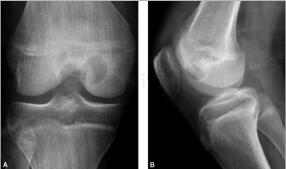

患者男,14岁,右膝伸直受限2个月余,伴关节周围肿胀,疼痛。病来无发热,无盗汗,饮食睡眠二便正常(图1~3)。

图1 DR:右股骨远端可见类圆形低密度影,边界清晰,可见硬化缘,软组织未见肿胀

图2 CT:右侧股骨内侧髁骨骺内见囊状密度减低区,大小约21mm×20mm,边界清晰,部分边缘可见硬化缘,CT值约为58HU,病灶内部可见少许点状钙化影。膝关节囊内可见积液影,周围软组织未见明显肿胀